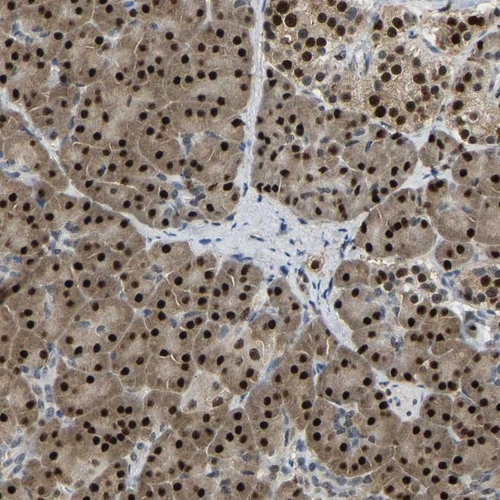

Immunohistochemical staining of human Pancreas shows strong nuclear positivity in exocrine glandular cells.